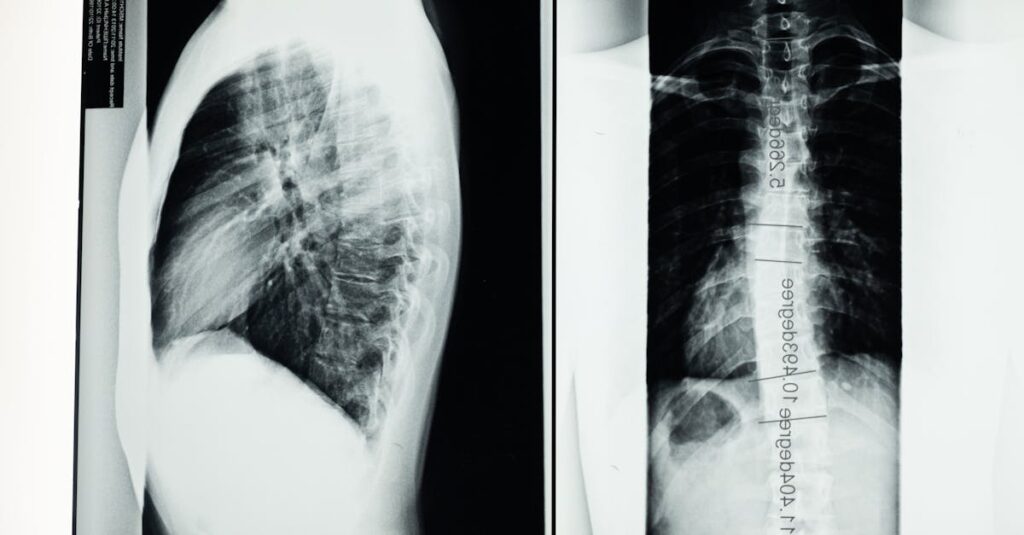

Quels examens permettent de diagnostiquer la sciatique?

Une IRM ou une radiographie est généralement nécessaire pour confirmer la cause de la sciatique.

Quels examens sont nécessaires avant de commencer un traitement de décompression pour la sciatique?

Une IRM ou une radiographie est généralement recommandée pour évaluer l’état de la colonne vertébrale.